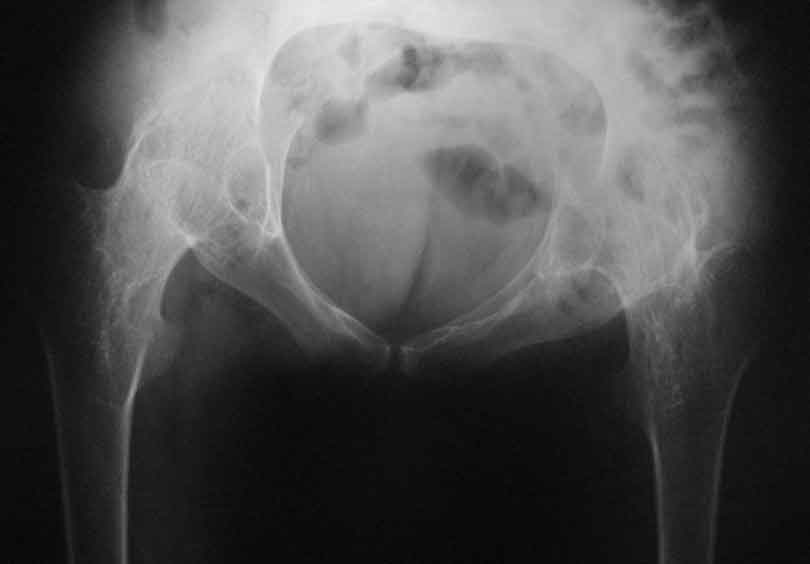

Уважаемые коллеги, в отделении находится пациент 28 лет, страдающий ревматоидным артритом с детства. В настоящее время основной проблемой для него являются тазобедренные суставы - костный анкилоз в положении сгибания около 80 град.

Привет Максим. На двух анкилозах передвигаться крайне плохо. Раз ходит - то небольшая часть мышц окружности т.б сустава есть, это видно и на фото. Пошел бы по пути разанкилозирования и бесцементник с каждой стороны поочередно.

Максим, мы протезировали 2х подобных больных. В случае с семилетним анкилозом на фоне болезни Бехтерева функция сустава осталась значительно ограниченой, но больная вполне сносно передвигалась. В другом случае на фоне ревматоидного артрита 4х летний анкизоз у молодого парня получен очень хороший функциональный результат. В обоих случаях использовали бесцементные протезы.

Следует учесть тот факт, что нечто принимаемое за хорошую кость во впадине по рентгенограмме, может оказаться очень неприятной пустотой с порозными балочками. При выборе размеров чашки это следует учесть, а в целом результаты не разочаровывают.